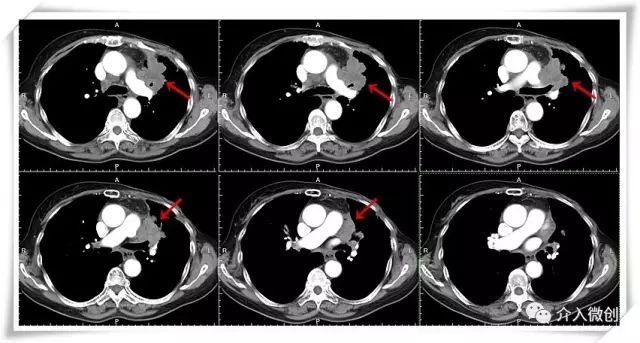

CT引导下放射性粒子植入左侧胸壁病灶及左肺肺门病灶

CT引导下放射性粒子植入左肺肺门病灶

DSA下行支气管动脉化疗栓塞术+留置导管持续化疗灌注术,进一步控制双肺转移病灶